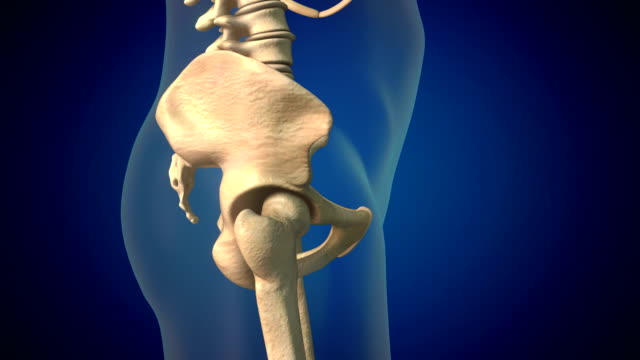

골반 통증에 좋은 운동 - 엉덩이 근육을 강화하는 운동

엉덩이 근육을 강화하는 운동은 골반 통증을 완화하는데 중요합니다. 대둔근이라고 불리는 엉덩이 근육을 강화하기 위해 다리를 뒤로 들거나 런지 운동을 실시하세요. 양쪽 다리를 균형 있게 강화하도록 노력하세요.

골반 통증에 좋은 운동 - 대요근·대퇴근막장근 스트레칭

엉덩이 뒤쪽 근육이 약해지면 앞쪽 근육이 긴장되는 경우가 많습니다. 따라서 엉덩이 근육이 아픈 부분을 스트레칭하여 이완시키는 것이 좋습니다. 예를 들어, 왼쪽 엉덩이가 아프다면 왼쪽 다리를 런지로 스트레칭하면 됩니다. 양쪽 다리를 균형 있게 스트레칭하면 골반 균형을 유지할 수 있습니다.